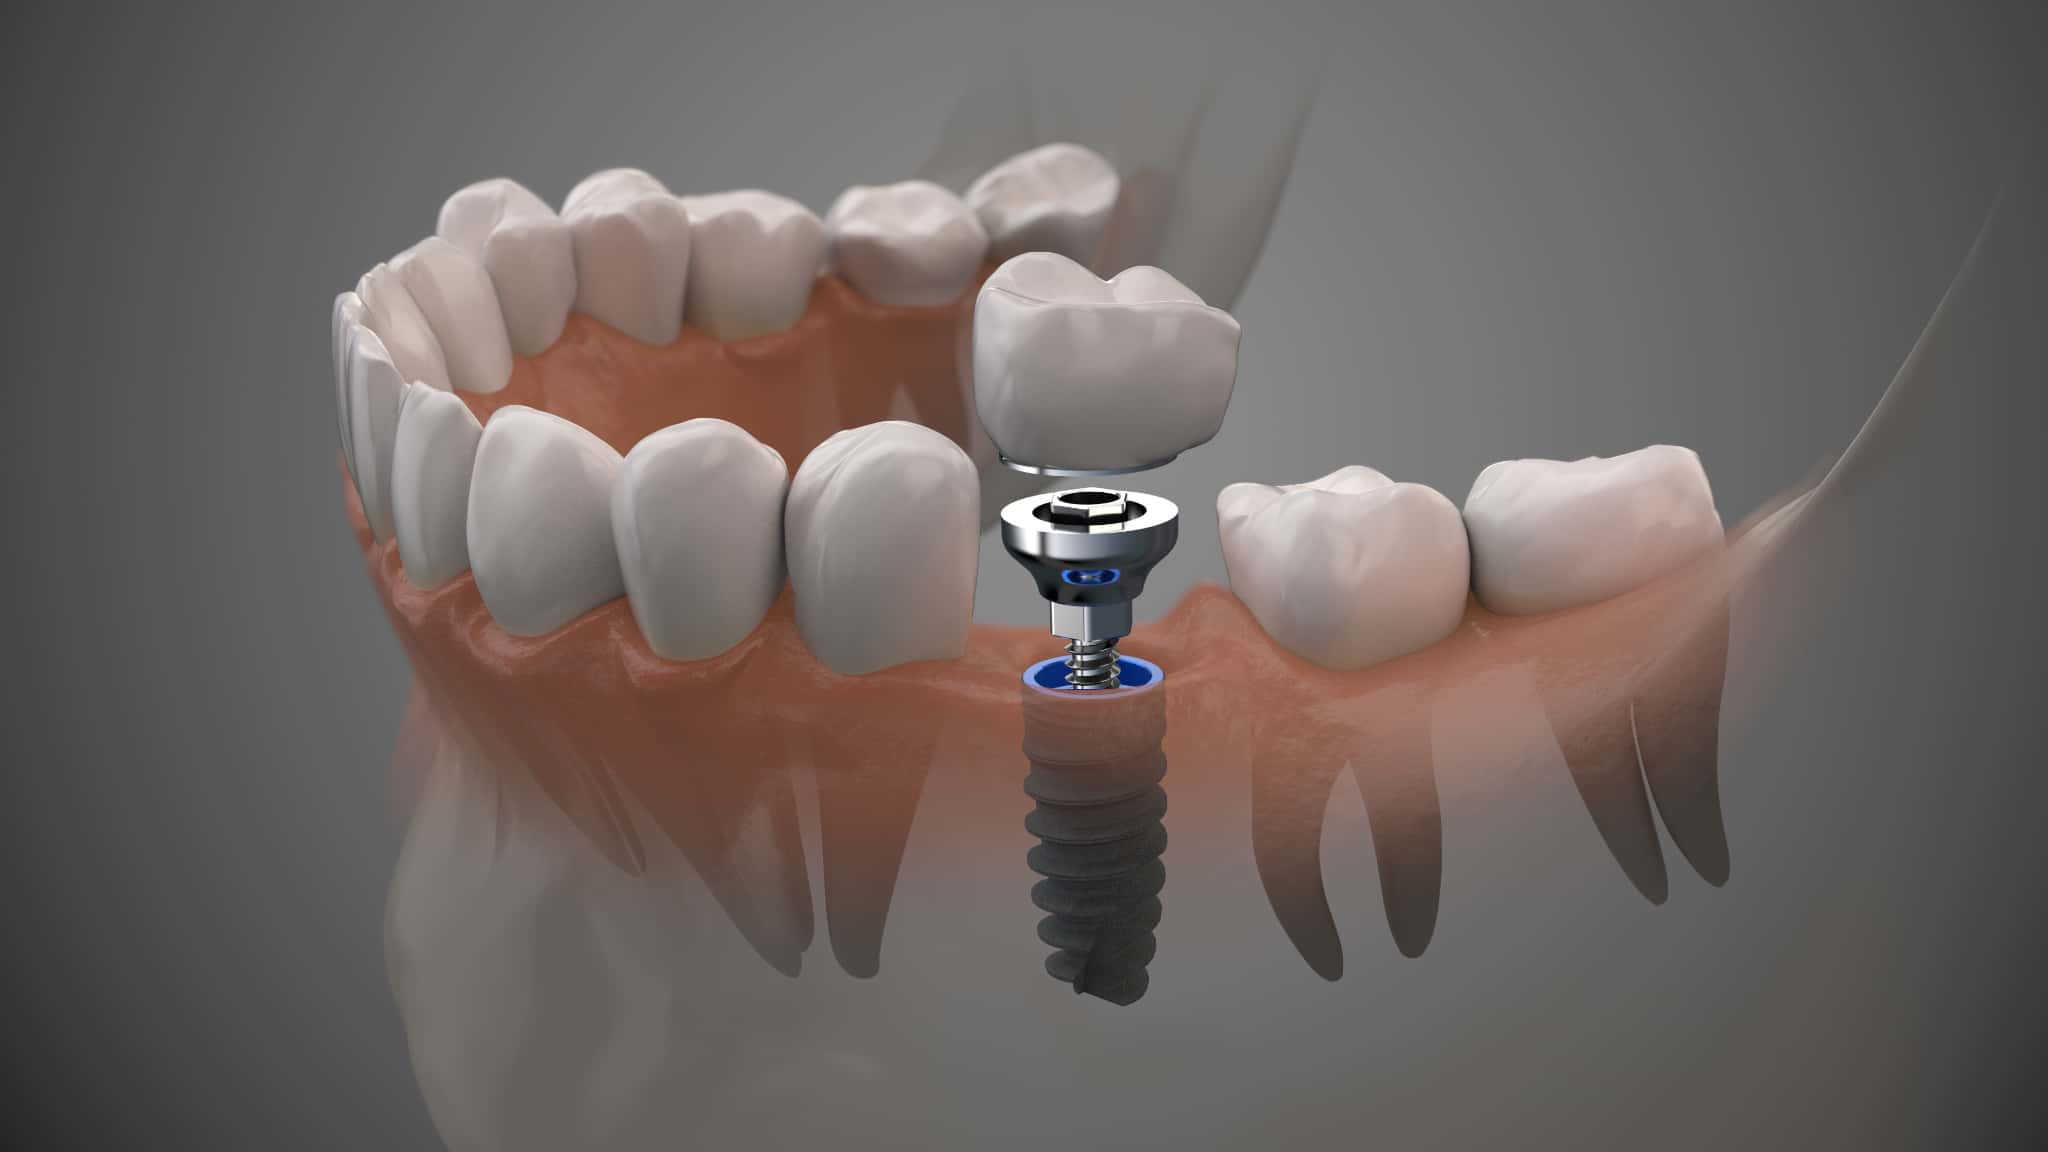

インプラント治療とは

インプラント治療は、顎の骨に人工歯根を埋め込み、その上に人工歯を装着することで機能と見た目を回復させる方法です。

この治療では、主にチタン製の人工歯根が使用され、骨と結合する性質を活かして安定した噛み心地を得ることができます。入れ歯やブリッジと異なり、周囲の歯への負担が少ない点も特徴です。また、自然な見た目に近づけやすく、審美面を重視する方にも選ばれています。

一方で、外科的処置を伴うため、術後のケアやメンテナンスが重要となります。適切な管理が行われない場合、歯茎の変色や炎症などのトラブルにつながる可能性があります。